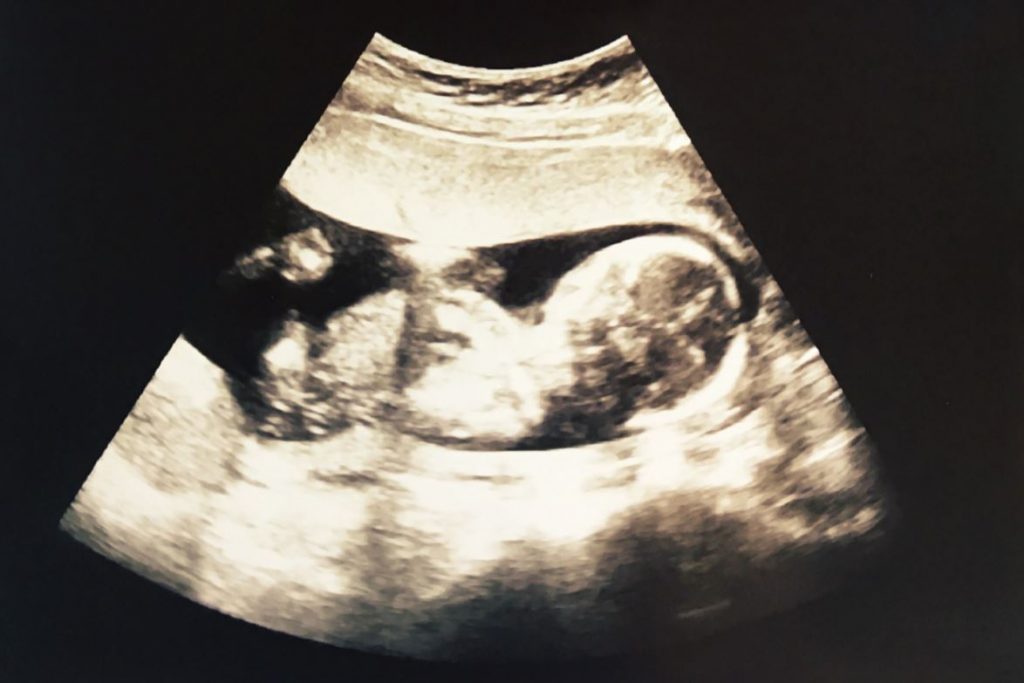

Le fœtus flotte dans le liquide amniotique. II est relié au placenta par le cordon ombilical. Son cœur bat à un rythme rapide, on écoute ses battements grâce à un capteur placé sur le ventre de la maman.

Ses formes deviennent plus harmonieuses : ses membres et son corps s'allongent, sa tête est proportionnellement moins volumineuse. Ses mains et ses pieds sont bien formés. Son visage continue à se façonner, son front est plus haut et son nez commence à bien se dessiner.

A seize semaines, le bébé mesure environ 18 cm et pèse environ 160 g.